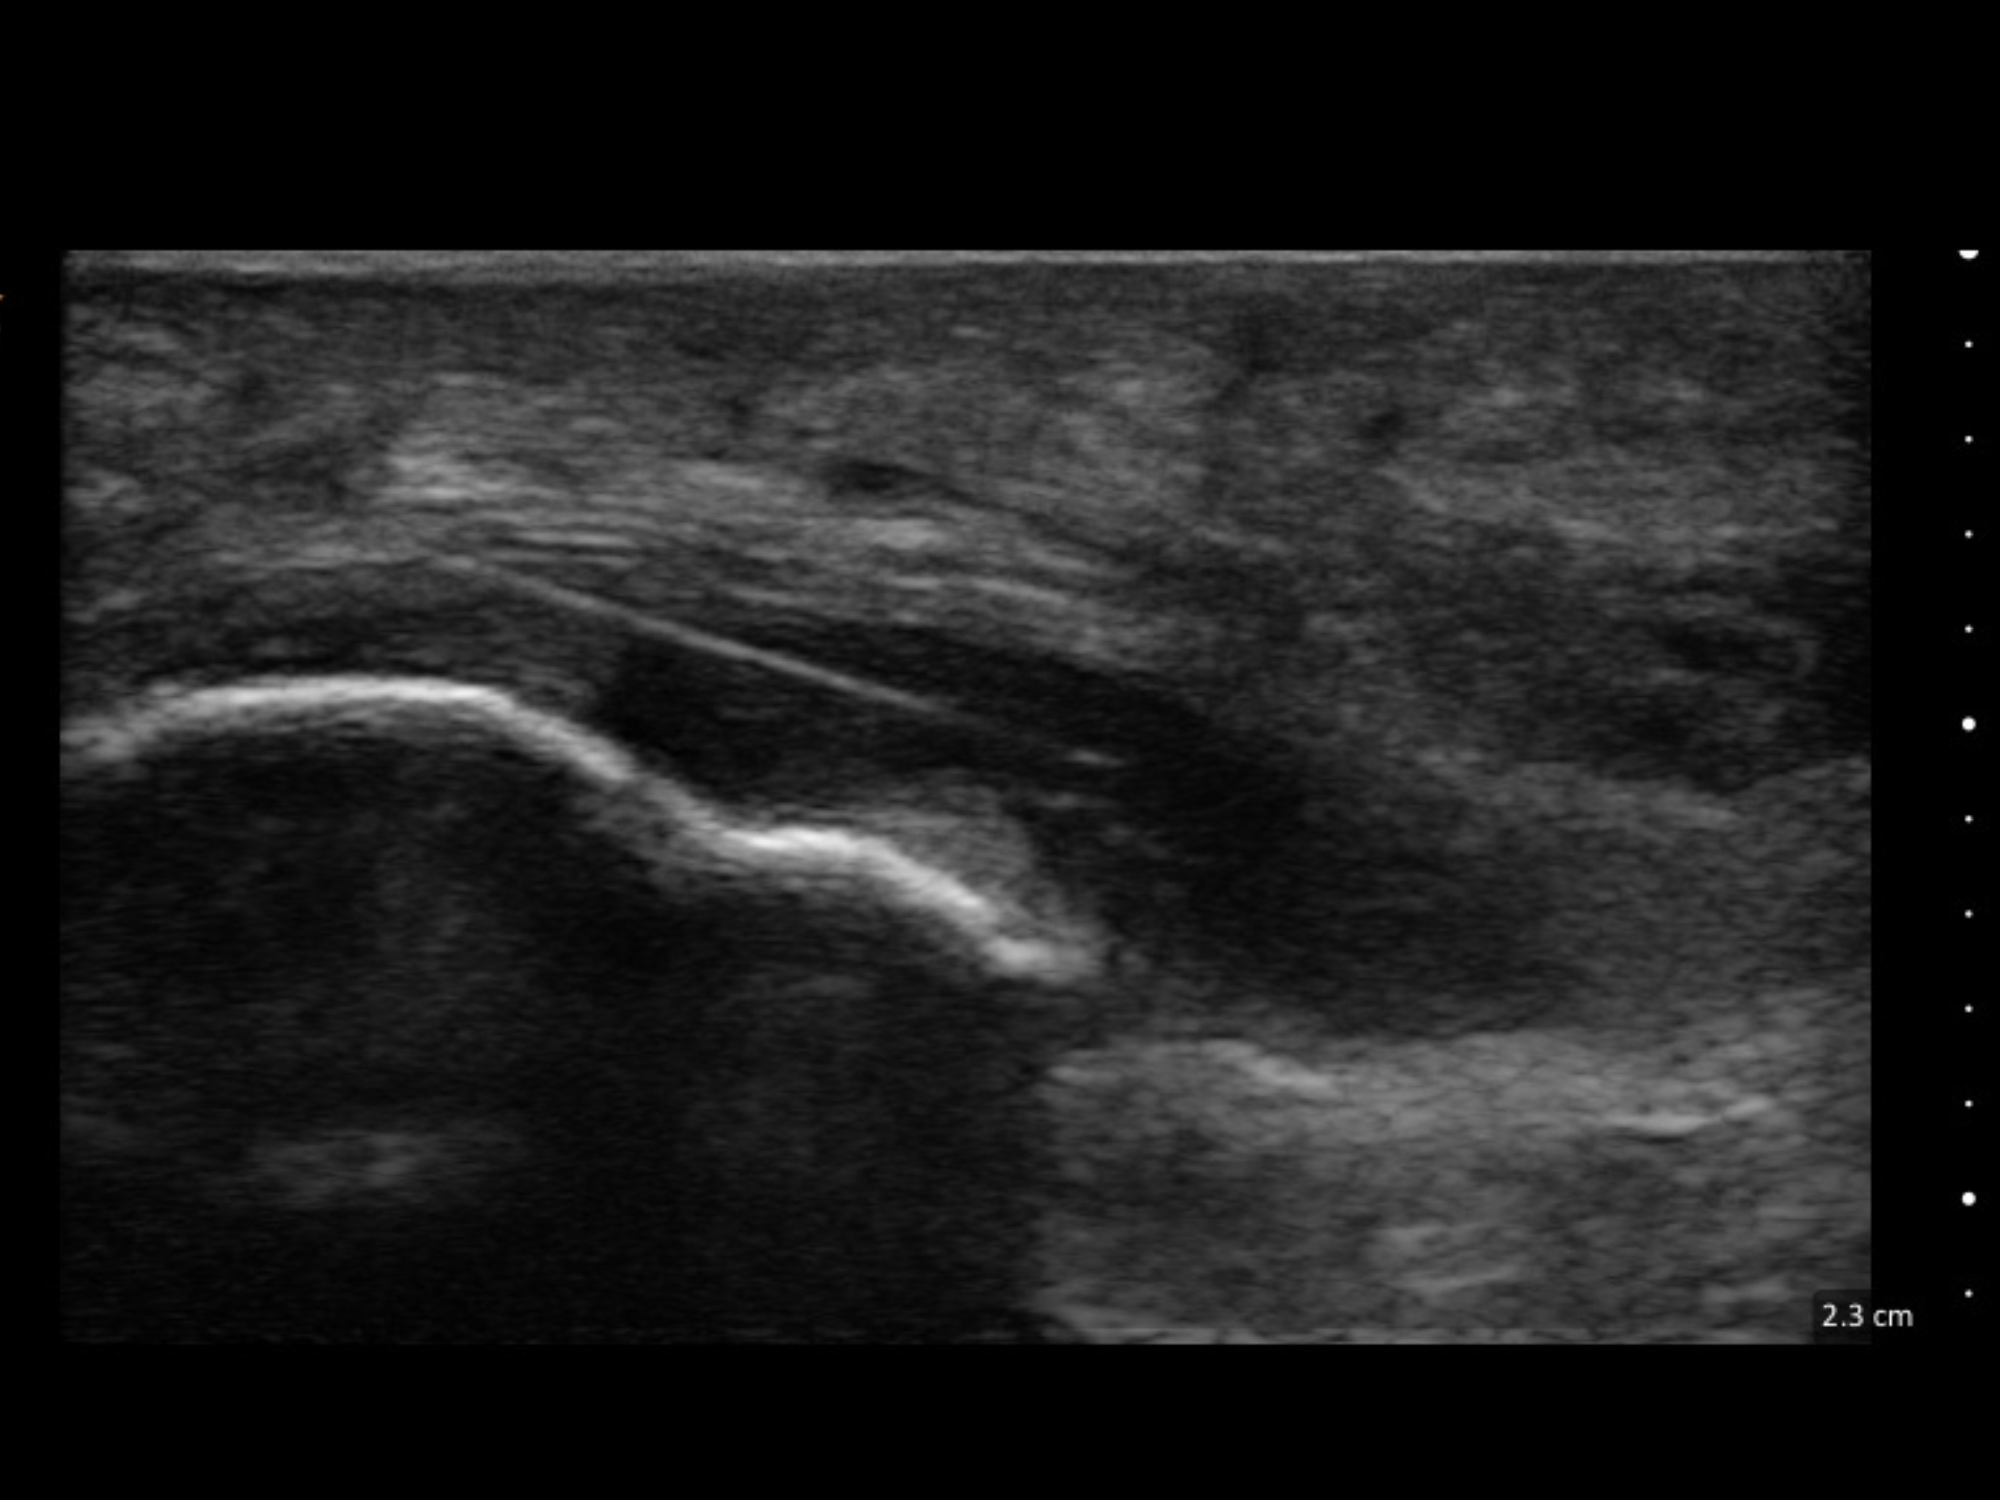

Ultrasound Guided Dry Needling combines real-time diagnostic ultrasound imaging with dry needling to help your provider accurately target specific muscles and tissues. This approach can be helpful when symptoms involve deeper structures or when precision matters most.

- Improved precision: Visualize deeper anatomy to guide needle placement

- More confidence in targeting: Useful when pain is complex or hard to reproduce